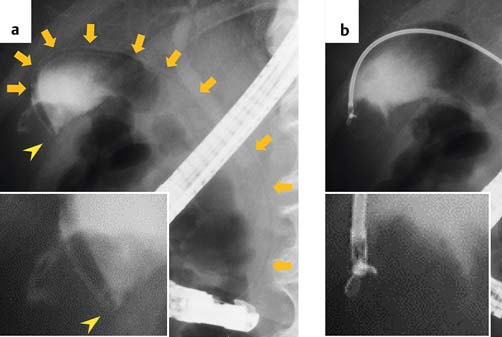

Fig. 3 Endoscopic retrograde cholangiography. a A guidewire was inserted into the gallbladder. b Contrast agent defect (yellow arrows) was observed at the gallbladder fundus.

图3. 经内镜逆行性胆管造影。a. 导丝插入胆囊。b. 在胆囊底观察到造影剂充盈缺损(黄色箭头)。

We placed a 0.025-inch guidewire into the gallbladder and inserted a biliary stent delivery system, composed of a guide catheter and pusher tube (MAJ-510; Olympus Medical Systems, Tokyo, Japan) (Fig. 4). After removing the guidewire and guide catheter, we inserted biopsy forceps (radial Jaw 4 Pediatric Biopsy Forceps; Boston Scientific Japan, Tokyo, Japan) through the pusher tube and performed biopsy of the gallbladder fundus legion (Video 1). The biopsy specimen was sufficient to diagnose gallbladder cancer (Fig. 5). Tumor recurrence was not seen for 3 years after surgery.

将一根0.025英寸的导丝插入胆囊,并置入一个胆管支架输送系统,该系统由一个导引导管和一个推送管组成(MAJ-510)(图4)。撤出导丝和导引导管后,我们通过推送管送入了活检钳(radial Jaw 4儿科活检钳),并对胆囊底部病变进行了活检(视频1)。活检样本充分,诊断该病变为胆囊癌(图5)。术后3年未见肿瘤复发。

Video 1 Biopsy of gallbladder tumor. a A pusher tube was inserted into the gallbladder (orange arrows) and the tip of the tube (yellow arrowhead) was located at the gallbladder tumor. b Biopsy forceps was inserted into the gallbladder through the pusher tube.

视频1. 胆囊肿瘤活检。a. 将一个推送管插入胆囊(橙色箭头),推送管的头端(黄色三角箭头)位于胆囊肿瘤处。b. 将活检钳通过推送管送入胆囊。